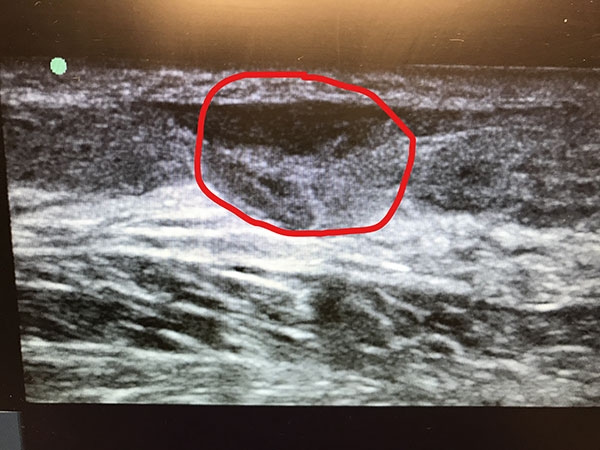

In-office ultrasound of Achilles Tear